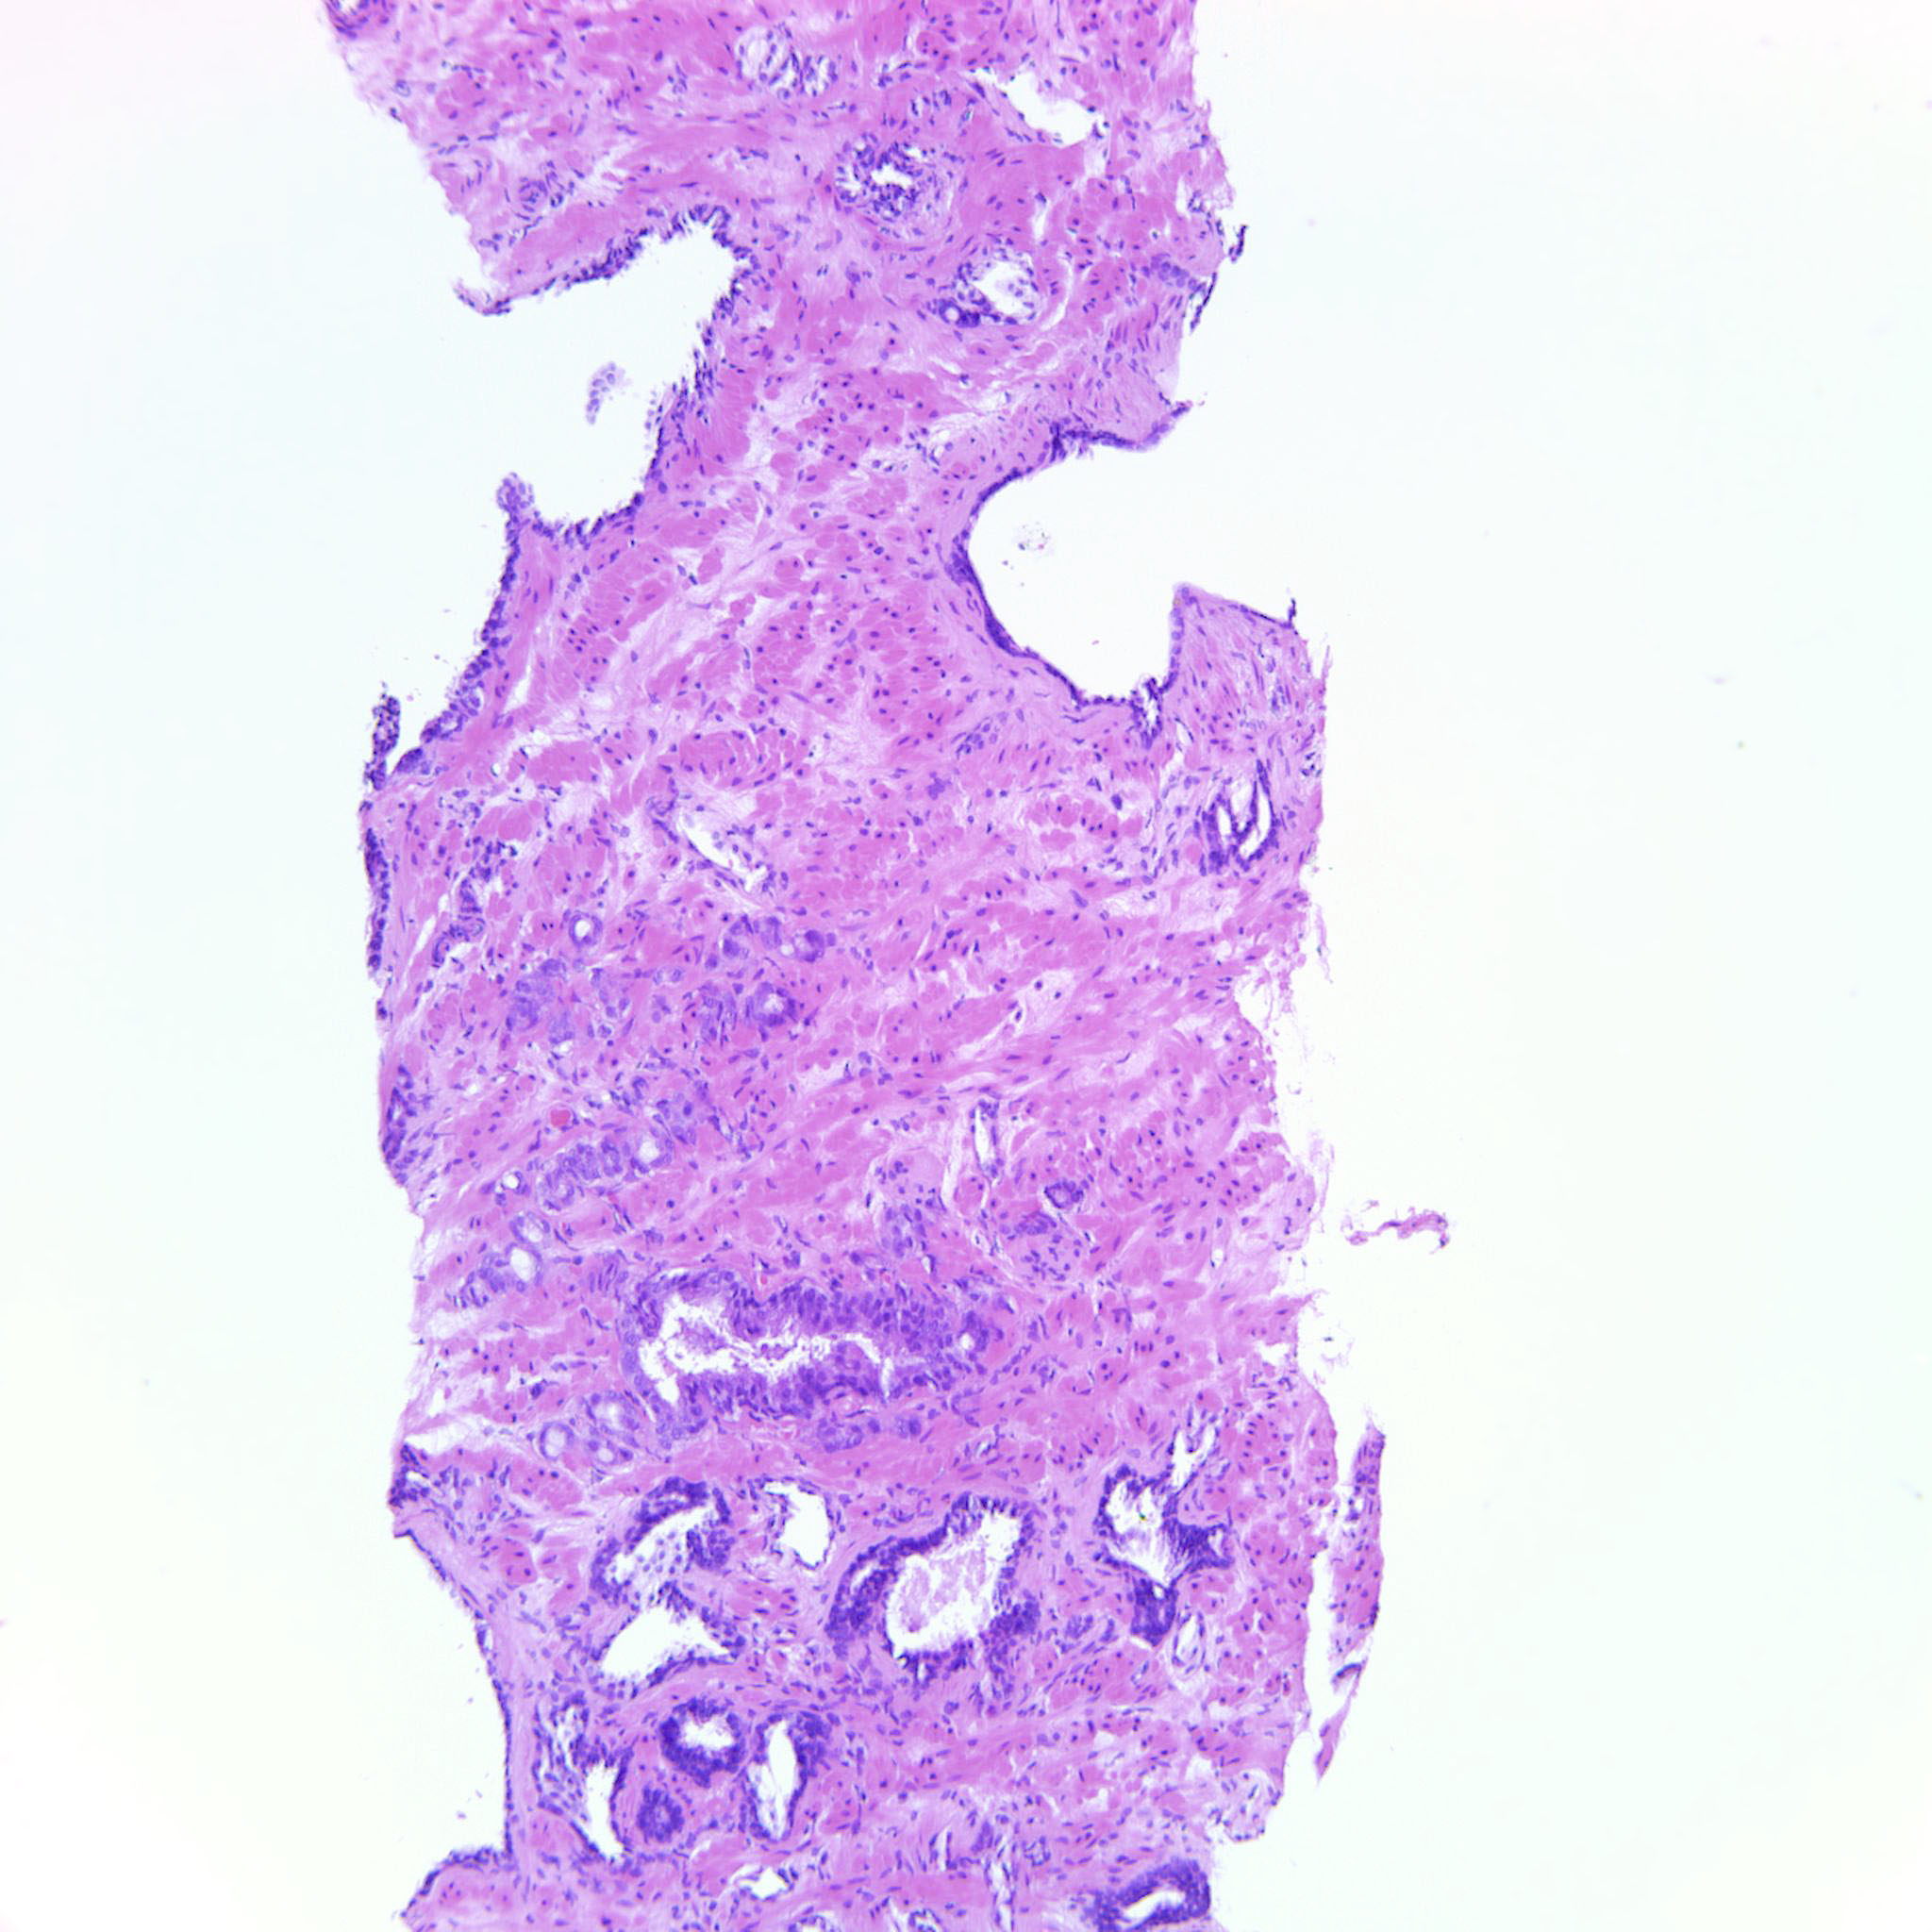

Prostate cancer grading

Case ID: 685